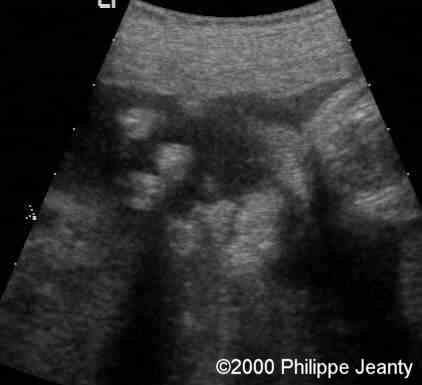

One hand demonstrated a clear simian crease

case0020-4

The other had both a simian crease and an unusual overlapping of the fingers viewed in this image and in the next (clinodactyly of the 5th finger)

case0020-4b

Other view of that same hand: note the clinodactyly.

case0020-5